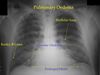

What are we looking for with a CXR

Pneumonia, infection Pleural effusion Pneumothorax Pulmonary edema Cancer, mass Heart size Mediastinum Perforated viscous Much, much more…